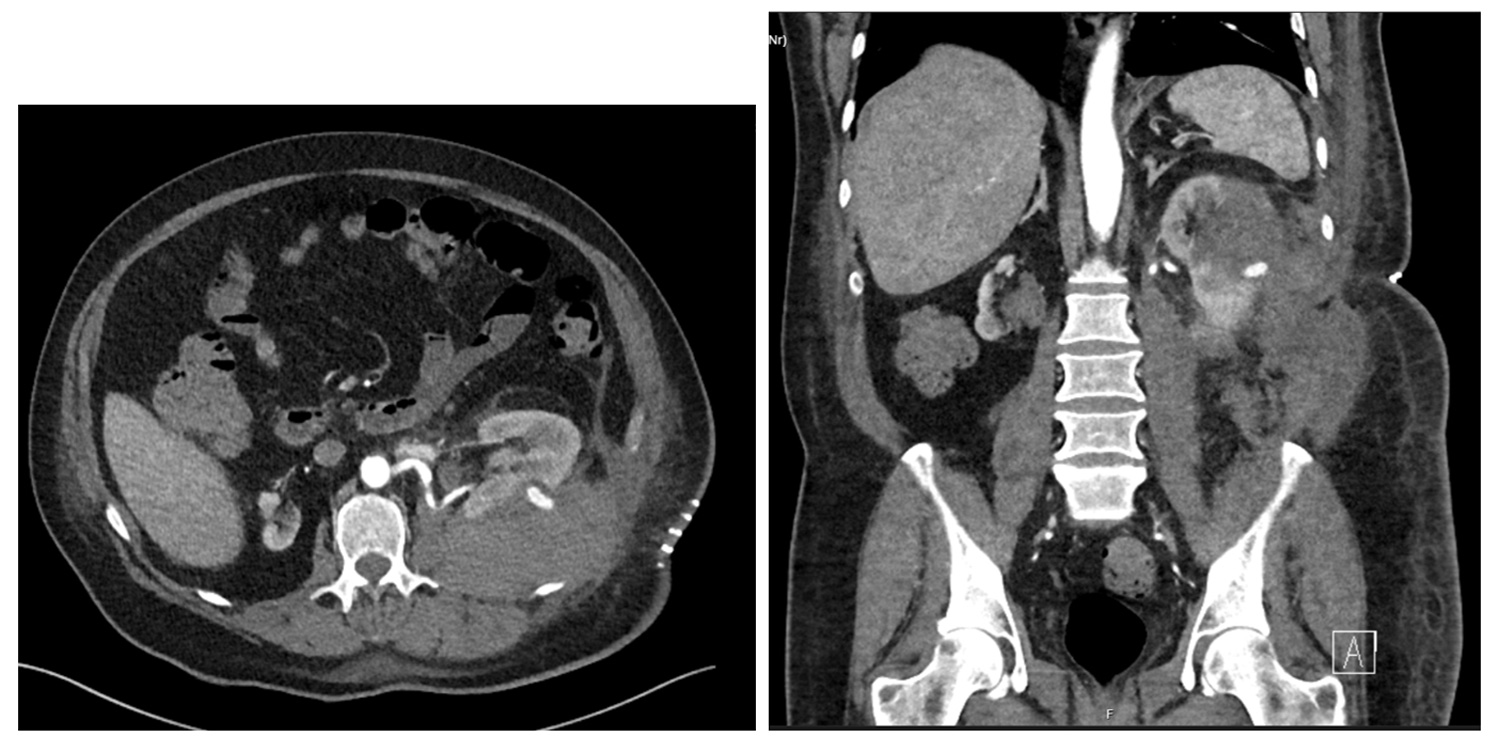

Figure 1: CT (axial and sagittal) views of the renal mass.

A 69-year-old male with a single left kidney underwent an open left partial nephrectomy for an incidentally diagnosed 5cm left renal mass with possible early collecting system invasion (stage T1b N0 M0) (Figure 1). Prior biopsy showed a papillary renal cell carcinoma type 1. This was found during investigations for episodes of macroscopic haematuria. He was known to have an atrophied right kidney since childhood. He was an ex-smoker (75 pack-year history) and other comorbidities included elevated body mass index (BMI) of 32.5, hypertension, and alcohol excess.

Ten days postoperative he presented to A&E at another hospital with tachycardia and with fluid leaking from his flank wound. Blood tests showed a Hb drop to 70 (from 100), AKI (eGFR 15), and subsequent CT showed a pseudoaneurysm extending from the posterior aspect with perinephric haematoma and haemoperitoneum (Figure 2). The collecting system was prominent. He underwent urgent angioembolisation with three microcoils injected into the two feeding vessels to the aneurysm, and was transferred to the intensive care unit (ICU). The phimosis was seen to have recurred and caused a degree of urinary retention requiring re-catheterisation.